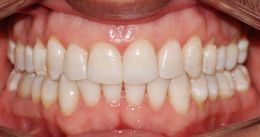

Paziente di 30 anni - Espansione dento-alveolare delle arcate e correzione affollamento grave con Invisalign; 48 mascherine; 2 anni di trattamento.

Giuseppe A. 30 anni

fine trattamento